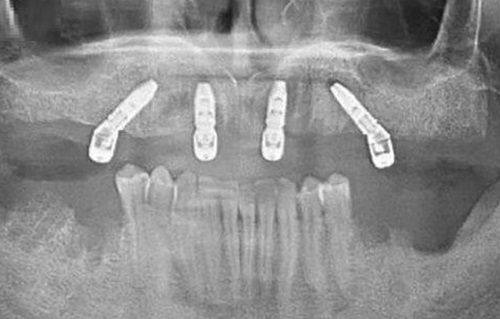

特别多人更关心的“种植牙装牙冠疼不疼”“种牙装牙冠疼么”这类问题,答案其实是几乎微痛。在安装牙冠前,医生会先通过专精检查确认种植体已经与牙槽骨完全骨结合,此时安装牙冠属于无创操作,不需要像种植体植入时那样切开牙龈、进行骨组织处理,也就不会产生明显的创伤性疼痛。

安装过程中,医生会根据患者的口腔咬合情况、天然牙形态精细调整牙冠的位置与角度,确保它和周边天然牙的咬合高度、邻接关系完全适配,整个操作相对简便,大多只需要打磨牙冠的细微部位或者调整粘接剂的用量,不会对口腔黏膜、牙龈组织造成刺激,所以患者基本不会感受到明显痛感或强烈不适,不少患者甚至形容这个过程就像给牙齿做了一次“精细微调”,轻松又快速。